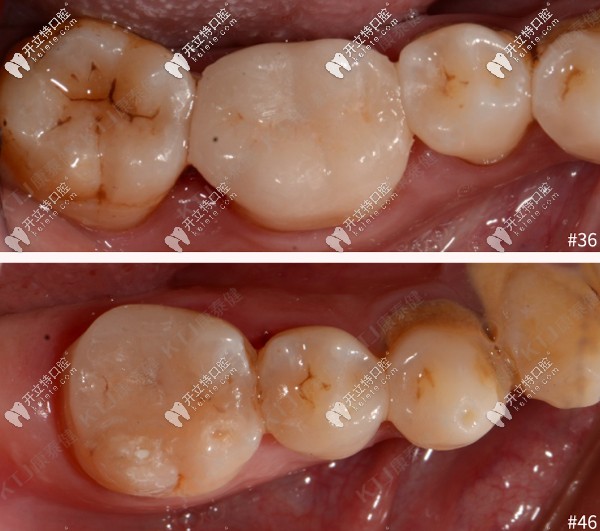

修復(fù)前后對(duì)比如下:

瓷嵌體修復(fù)前后對(duì)比